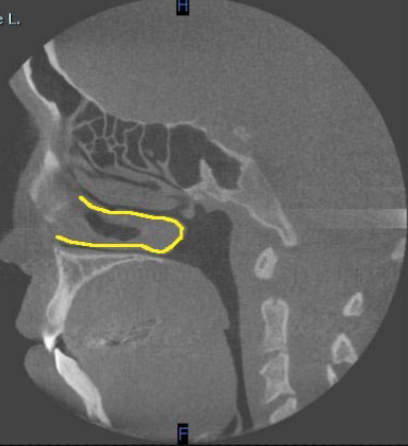

sagittal

what plane is this

inferior alveolar canal

identify the structure